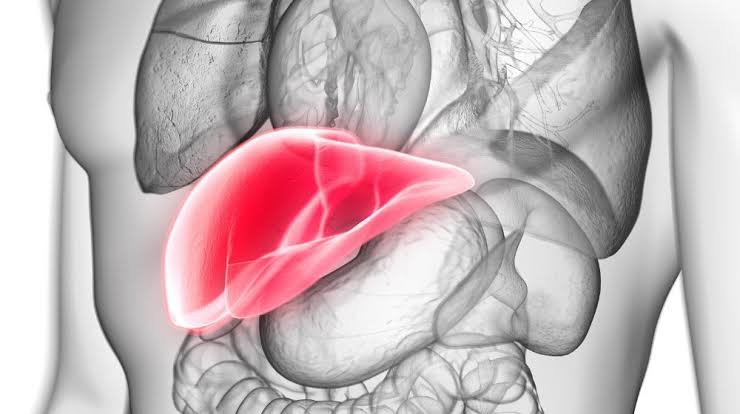

Liver, a key part of human digestive system, is an organ that is responsible for cleaning out toxins from our blood, processing medicines, producing bile, helping you digest fat, storing glucose and producing proteins for clotting your blood, among many other things.

It’s also a fairly forgiving organ, able to regenerate cells up to a point, but repeated damage to the liver leads to inflammation, scarring and cirrhosis. This causes it to shrink and harden, and changes the structure of the liver, preventing it from functioning well.

A high intake of alcohol or toxins, a diet high in fat, and some viral infections, such as hepatitis, can cause damage to the liver. Liver disease doesn’t usually cause any symptoms until the damage to the liver is fairly advanced. Some signs your liver may be struggling are: